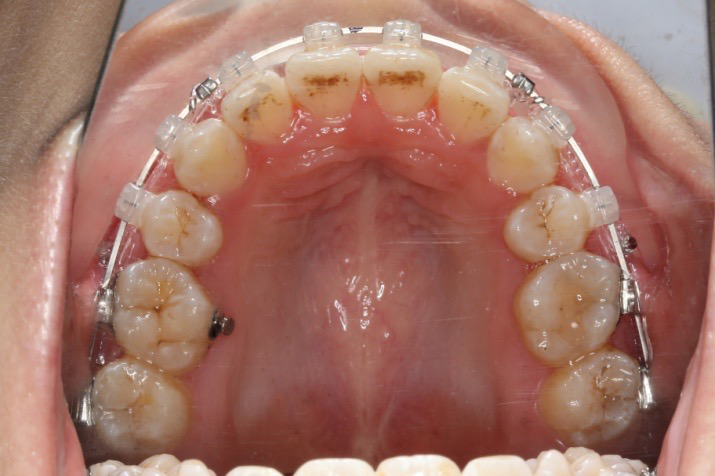

2016.10.31  初戴,0.013cu-niti2017.1.13  上颌加TPA,U56间斜形植入韩国庆北1312-08种植钉,上下0.16cu-niti

2017.02.16  上下0.014*25 cu-niti,50g 拉尖牙远中

2017.04.28

2017.04.28  上0.016*25ss 13、23近远中约5度 v形曲,下0.017*25ss